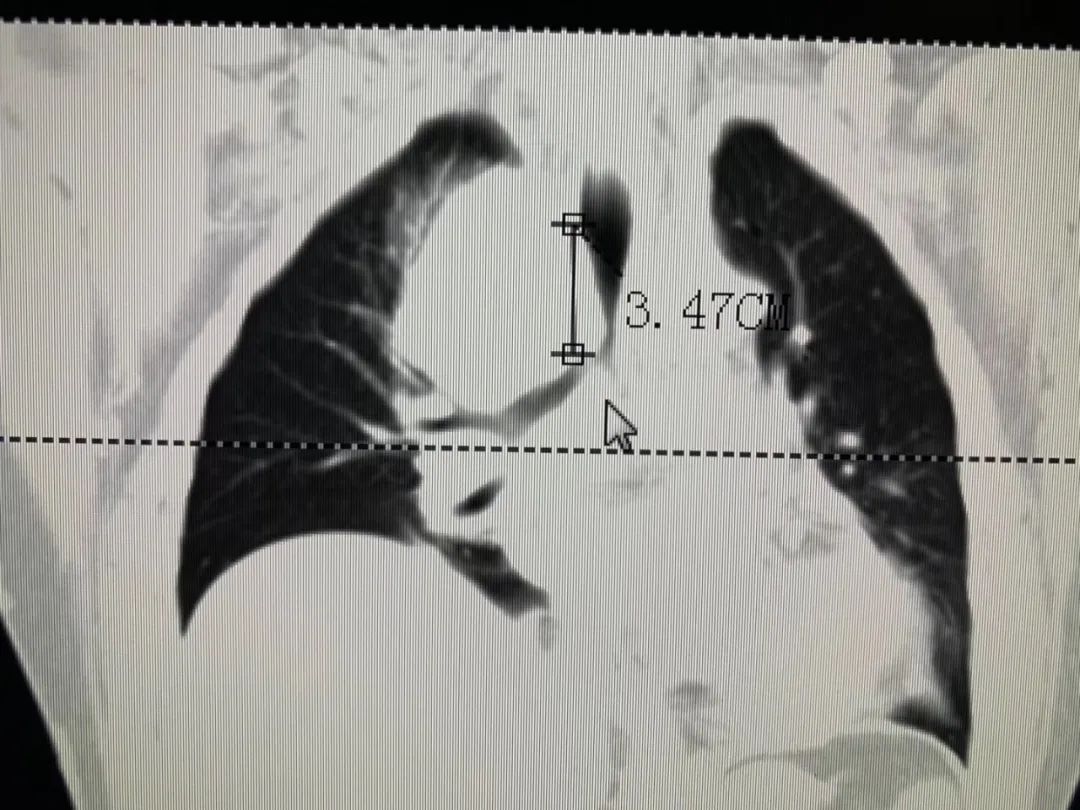

患者金先生因吃饭吞咽困难去当地医院做电子胃镜检查,确诊为食管癌,情况很不乐观。为求进一步诊疗,金先生先在我院接受了两次食管癌介入化疗,控制肿瘤发展,改善吞咽困难情况。

牛立志院长表示,患者无手术指征,而介入治疗副作用小,患者易于耐受,在改善晚期食管癌患者生活质量的同时,延长患者生存期。此外,术前新辅助化疗可以达到明显降期目的,为根治术手术创造条件。随着金先生身体逐渐变好,牛立志院长、曾宗渊名誉院长为其开展右侧开胸食管癌根治术+三野淋巴结清扫术,经过9个小时手术顺利完成。